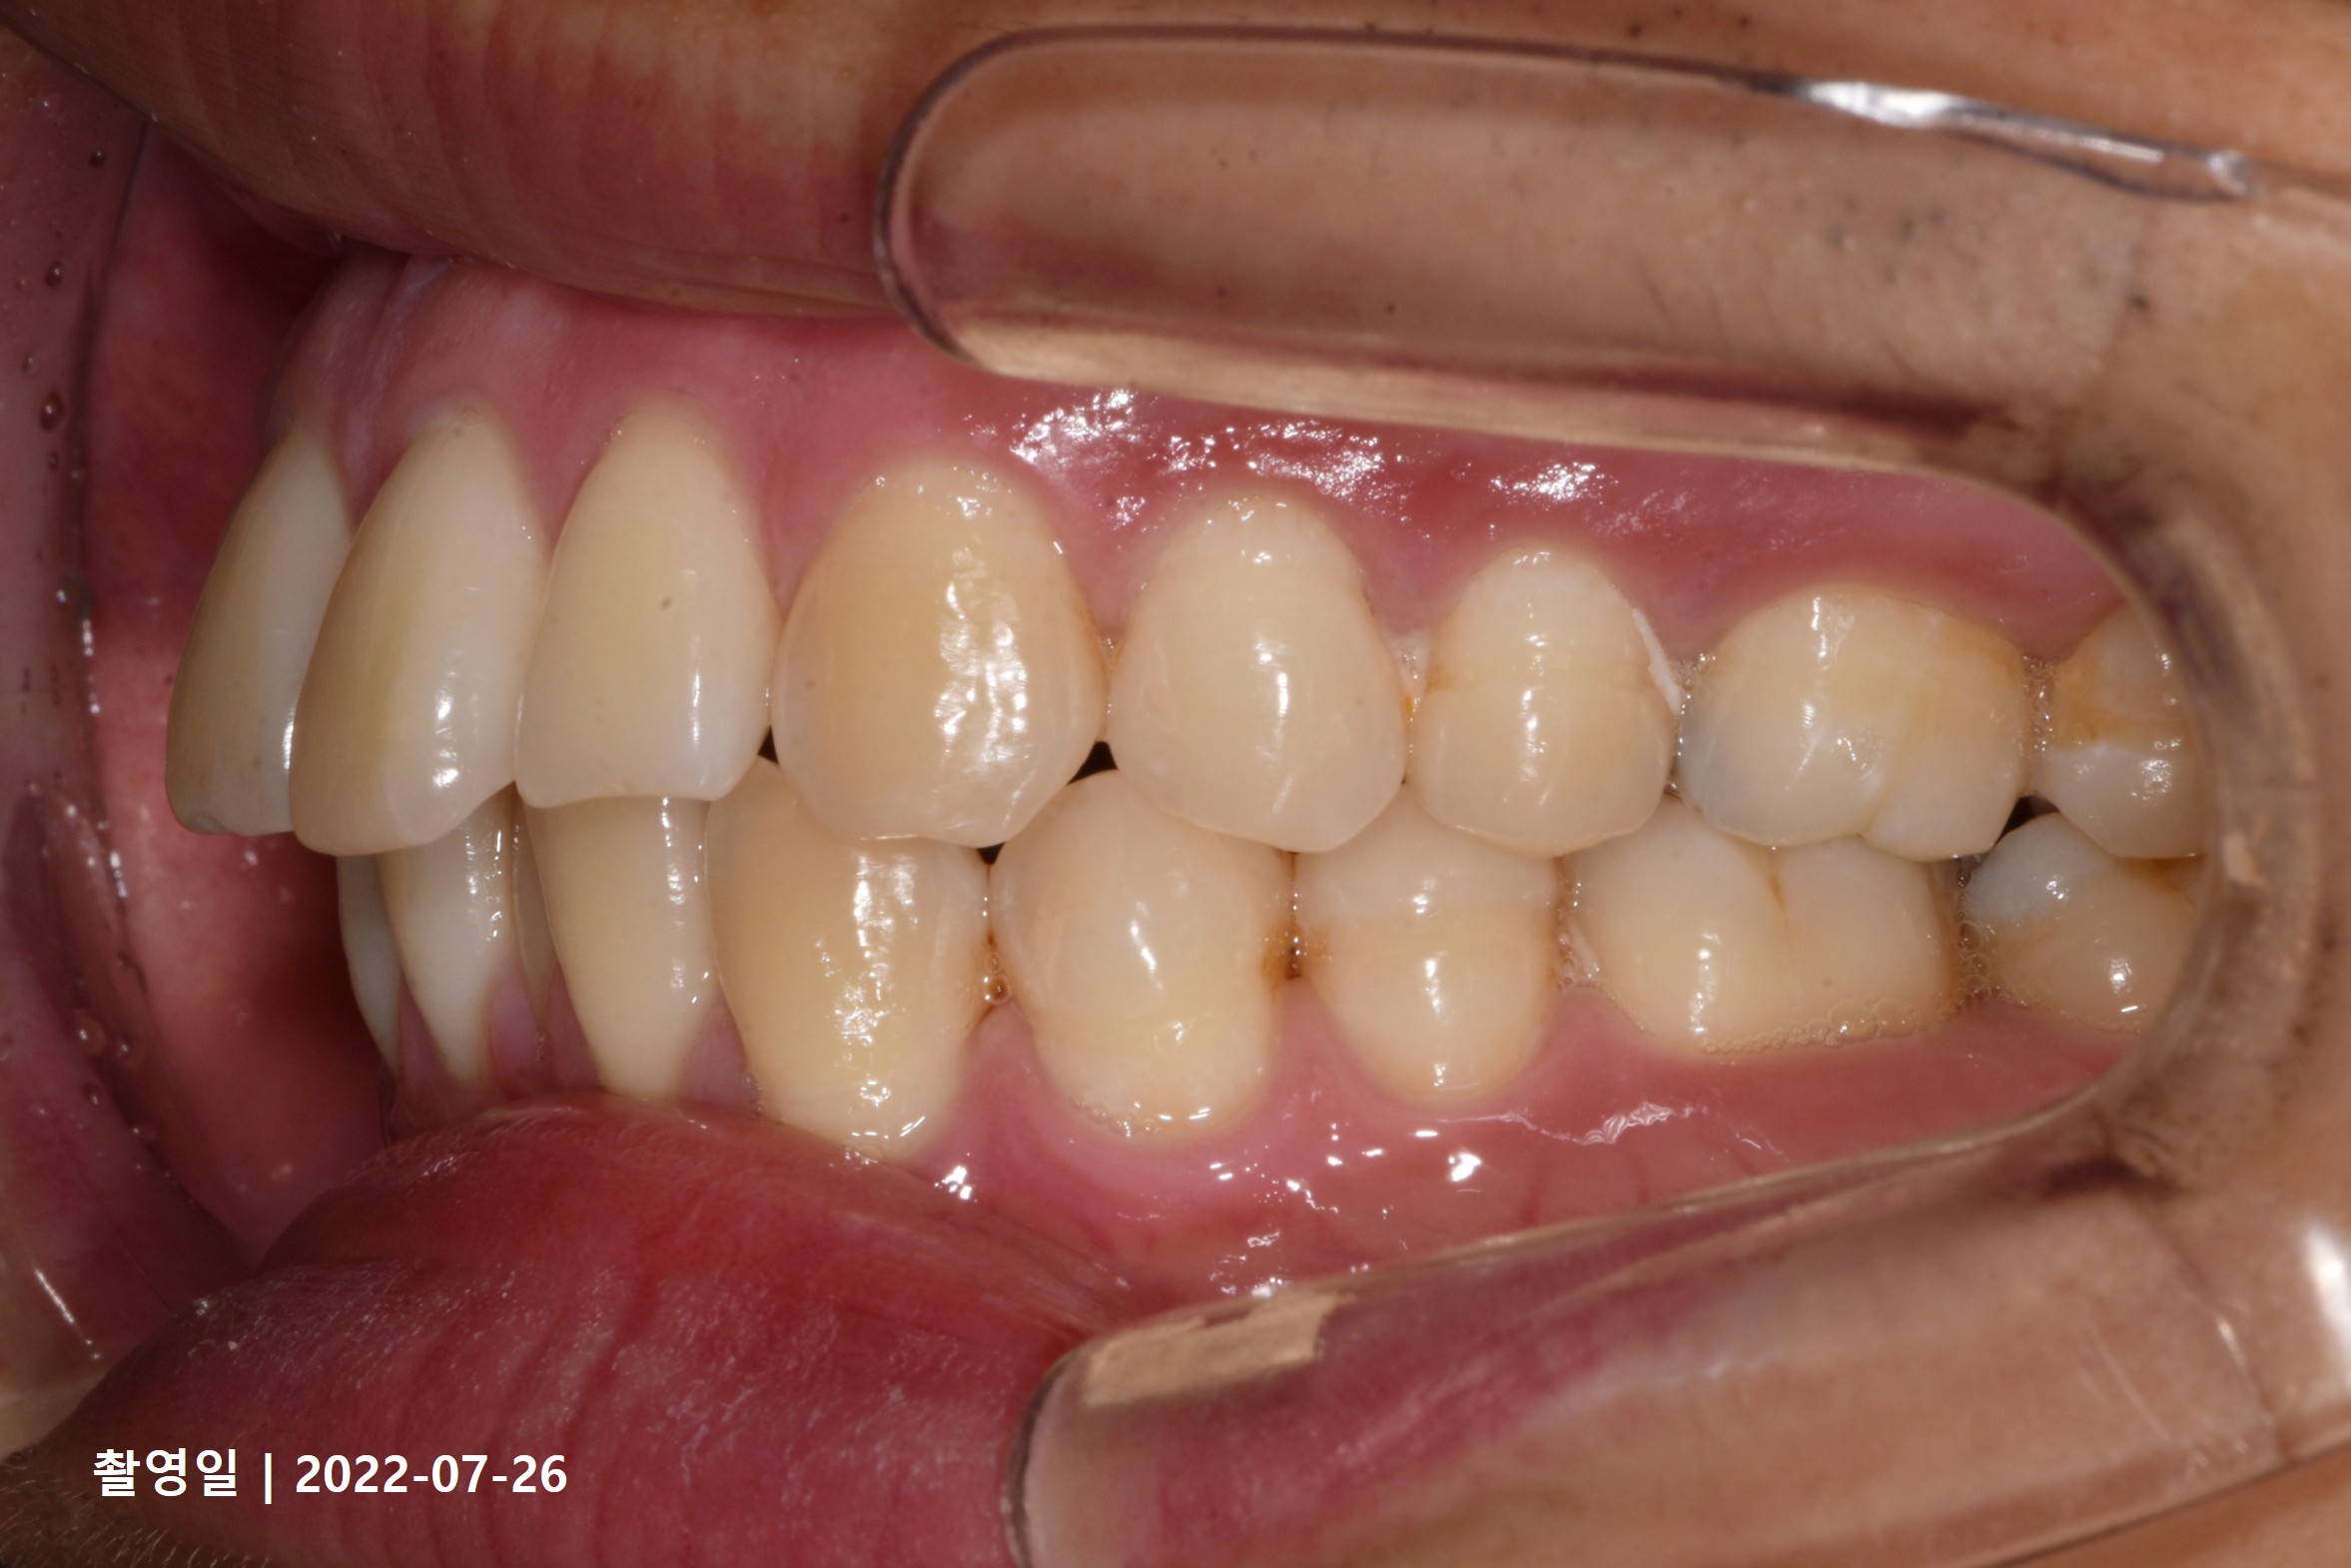

Case 4

- 19세 여성

- 상하악소구치 발치

- 치료기간 2년 8개월

치료 전

치료 후